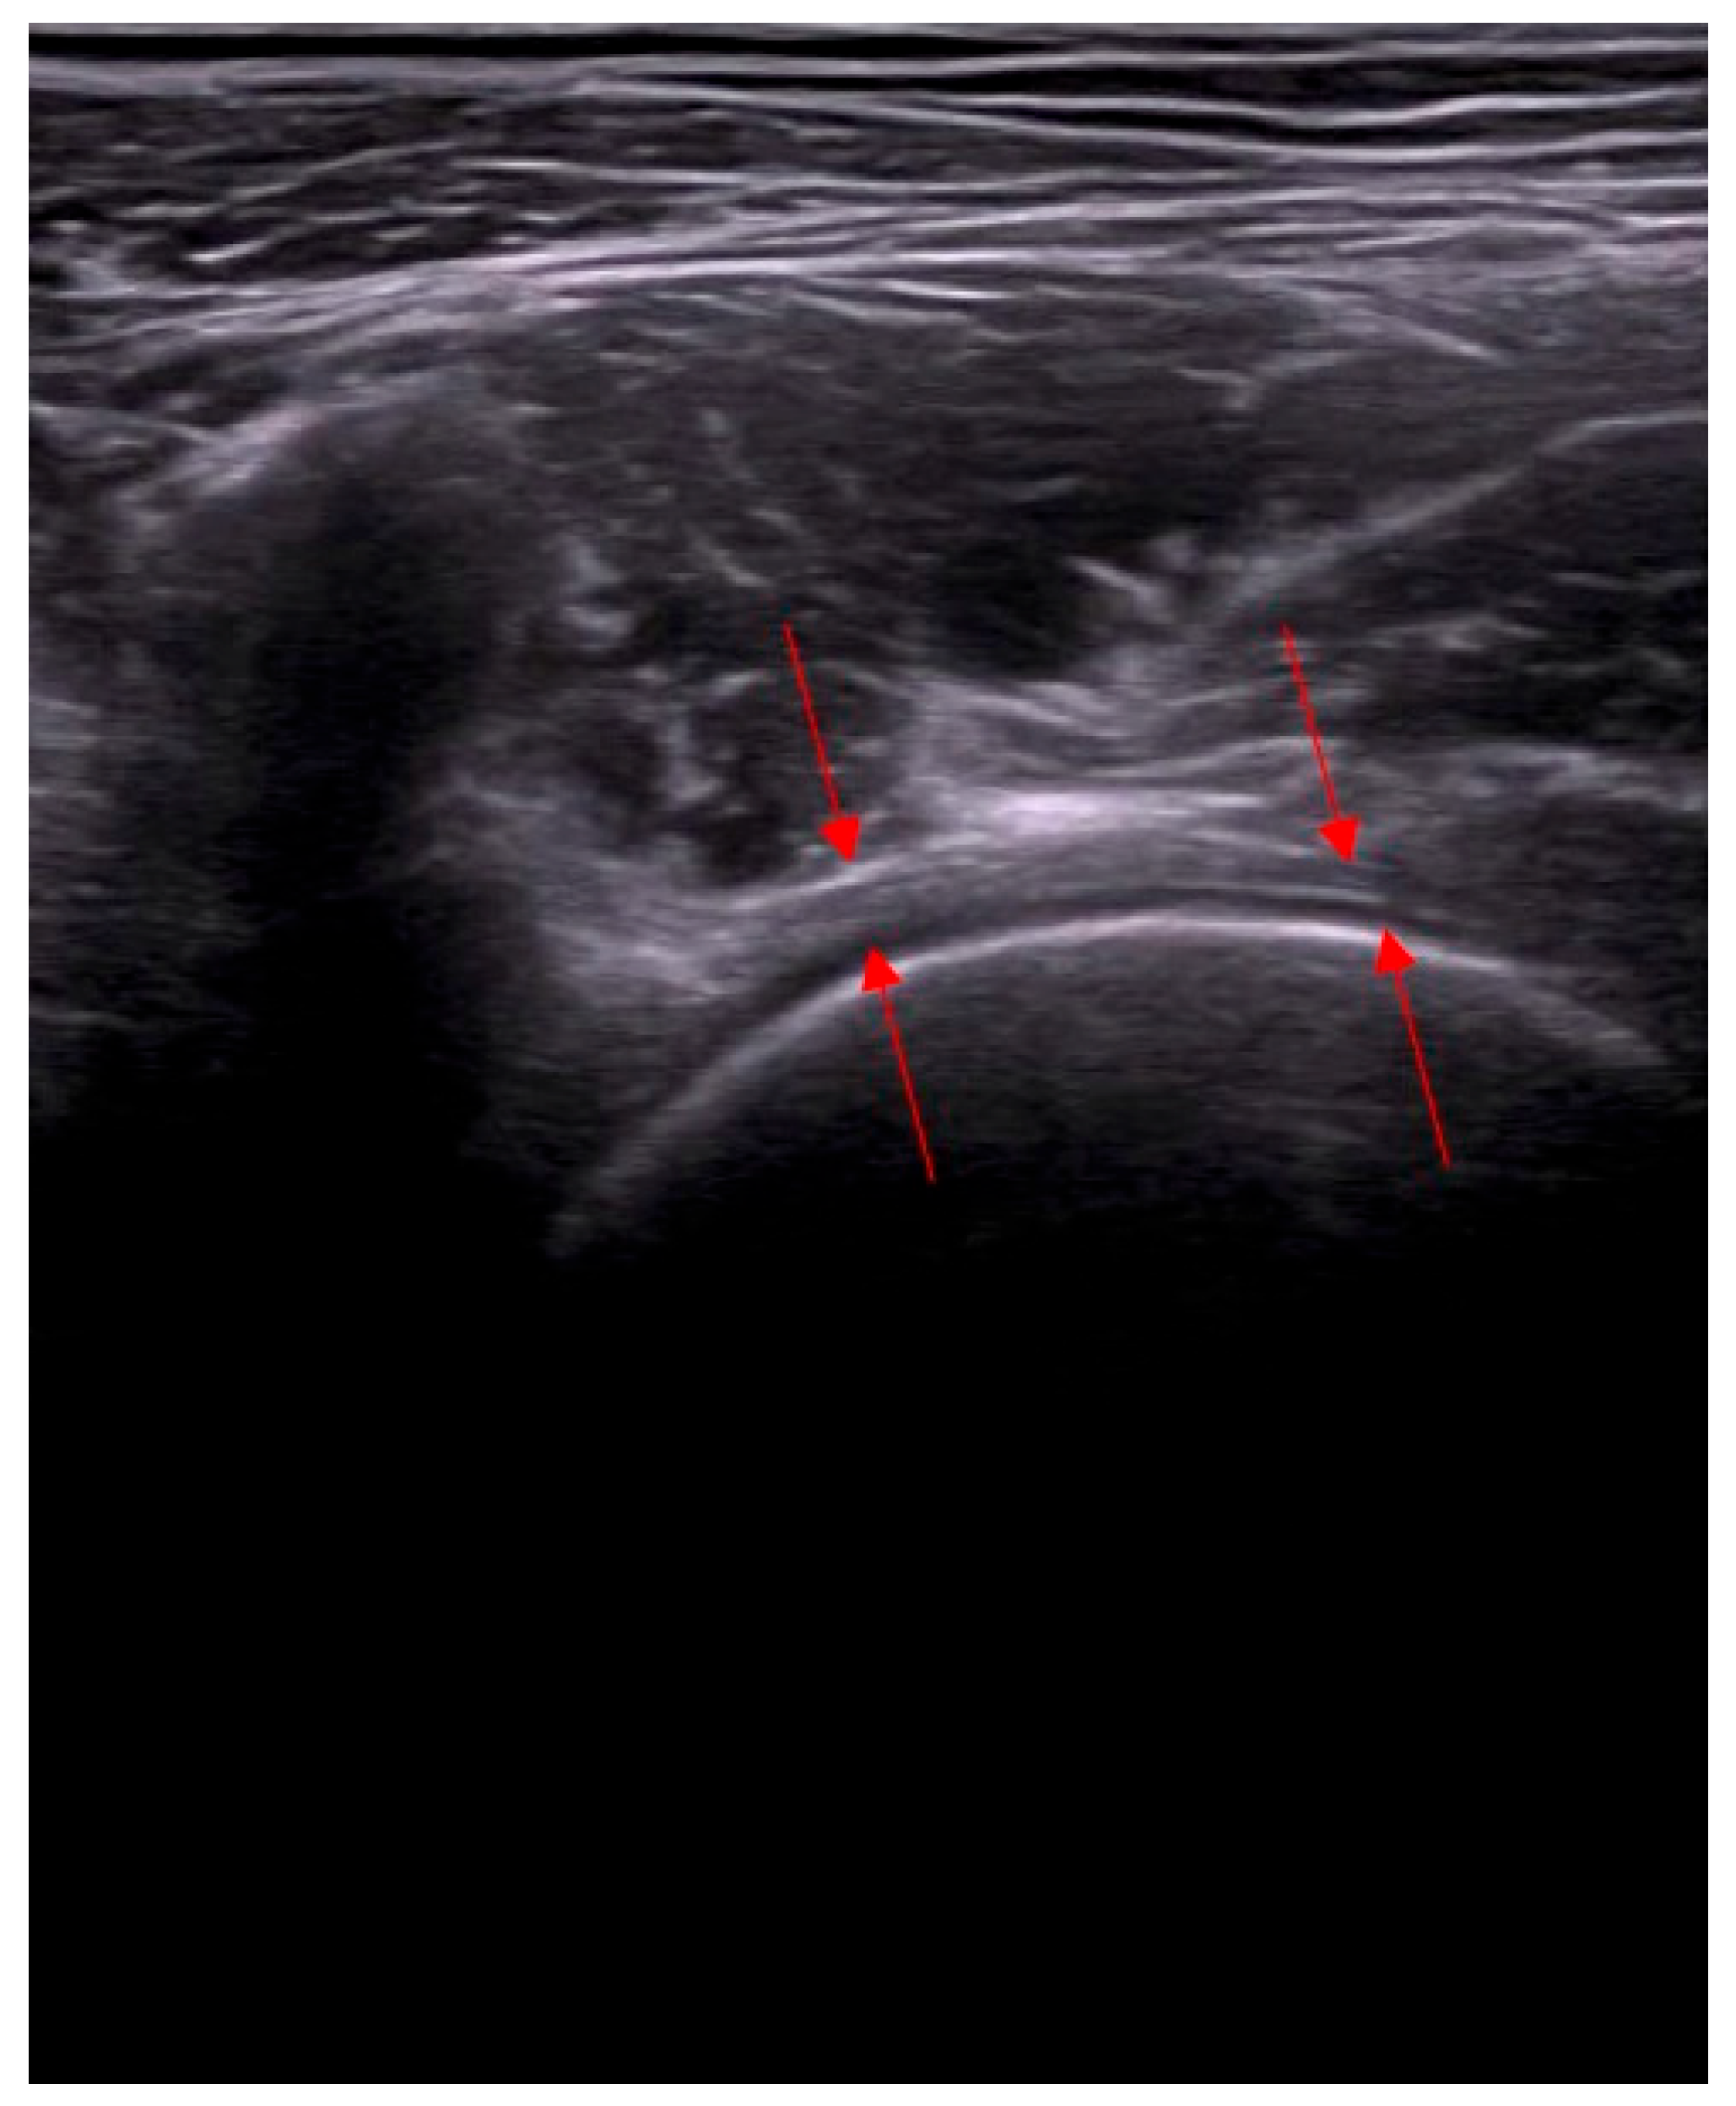

- Assessment of capsular adhesion thickness—ultrasonographic evaluation was performed with the probe positioned transversely, allowing for precise visualization of adhesions. The most common location of adhesions was in the anterolateral complex, with less frequent occurrences in the medial complex.

- Anterior capsulotomy location—the procedure could include a capsulotomy at the equator of the femoral head in the transverse ultrasound view. Optional additional approaches included a medial approach relative to the neurovascular bundle.